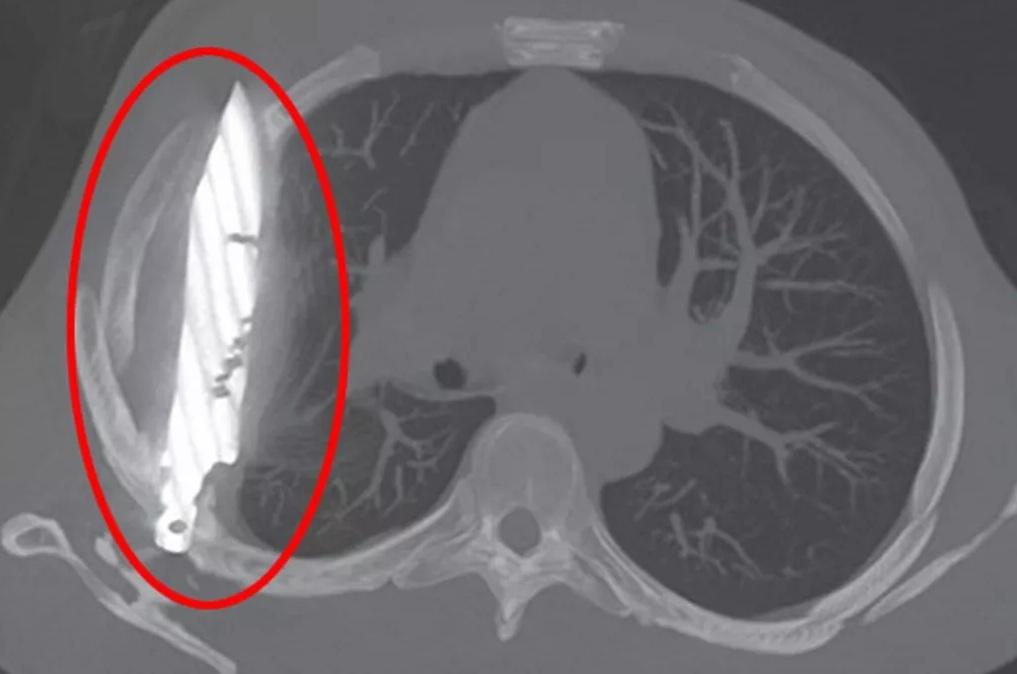

胸部X光檢查結果顯示,有一把刀插在病人胸腔內。從X光影像可見,這把刀從右肩胛骨插入,奇蹟地避開重要器官。